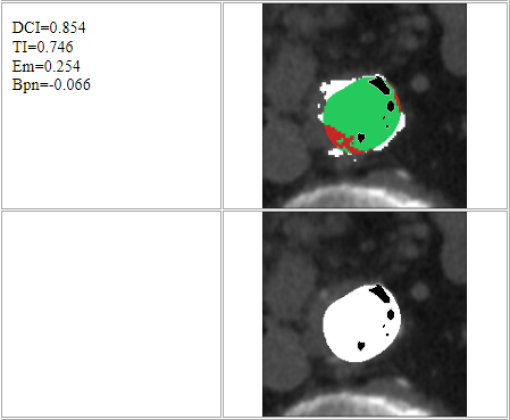

At this point, the dataset is ready for the processing in the portal ImageLab. The latter, takes as input the basal ROI and its corresponding CM one, together with their respective binary masks. These, are used by the algorithm to create the image (see Fig. 2), and consequently to detect the vessel. As depicted in Fig. 4, in output the extracted image is provided, along with a colored map where green highlights pixels correctly classified by the algorithm, red indicates misclassified ones, and white indicates the areas the algorithm should have identified but did not. Adjacent to this, similarity indices described before are presented, computed by considering the CM image as the target, which is provided as input for this purpose. We have processed in the portal each slice of our dataset.

In this version of the algorithm (updated compared to the one described in [30]), the calcium plaques are excluded from the patent lumen of the vessel and therefore visible in the processed image (in black), as we can observe also from Tables 3 and 4. The advantage of removing these structures during the extraction process leads to a more accurate and faithful evaluation of the indices. This observation is illustrated in Figure 6, where we present a comparison of results for a single slice obtained using the previous algorithm version, which does not remove calcium plaques from both the basal and the CM images, and the new algorithm version. The performance improvement is evident, particularly in the DCI index, where a difference is observed: of white pixels are accurately classified with the old version, compared to with the new version. Finally we highlight how, in the new version of the algorithm, the removal of the calcium plaques from both the basal and the CM images produces a different extraction of the patent lumen of the vessel, which in addition to being compatible with the algorithm’s steps, also turns out to be more accurate.

| Basal image | CM image | Version | Extracted | Colored map | Indices |

![]() |

Old | ![]() |

DCI: 0.824 |

| TI: 0.700 | |||||

| Em: 0.300 | |||||

| : -0.192 | |||||

| New | ![]() |

DCI: 0.894 | ||

| TI: 0.809 | |||||

| Em: 0.191 | |||||

| : -0.075 |